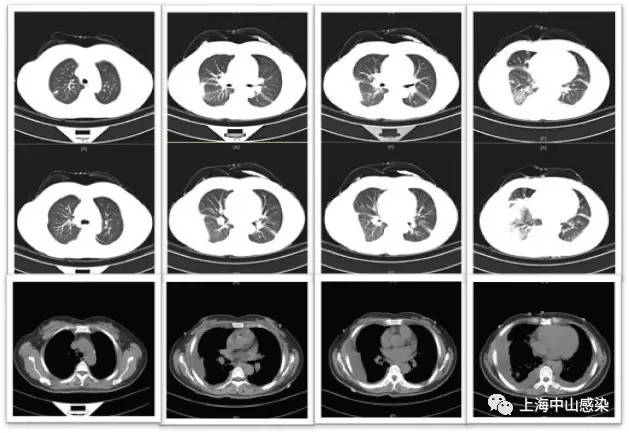

6月14日复查胸部CT2:肺炎稍吸收,但双侧胸腔积液更加明显

肺吸虫血清抗体阳性,诊为肺吸虫病,吡 喹酮1g(200mg*5片),tid,3天,8.29 CT3复查病灶明显吸收。

2.本例有意思的地方是有不符合常见寄生虫病的特点:血嗜酸性粒细胞不高;血IgE正常;胸腔积液无嗜酸性粒细胞;肺内未见虫体移行性空洞或囊性病灶;但也有多处提示:多浆膜腔积液;抗菌治疗无效;肺内病灶呈游走性;患者喜食醉蟹。

CT1.jpg

CT2.jpg

CT3.jpg